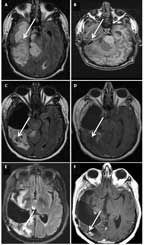

FIGURE 5

MRI of a 42-Year-Old Man With an Anaplastic Oligoastrocytoma, IDH1-Mutant and 1p/19q-Maintained

A 42-year-old man presented with a headache and visual disturbances. MRI revealed a large, nonenhancing, T1 intrinsically hyperintense, 10.6 × 6.7 × 5.2-cm mass involving the right temporal and occipital lobes, with exophytic components (Figures 5A and 5B). The patient underwent partial resection (Figures 5C and 5D). Pathological and molecular analysis revealed an anaplastic oligoastrocytoma, IDH1-mutant and 1p/19q-maintained. He received 10 cycles of adjuvant temozolomide, and was then observed. Two years later his disease progressed and he was rechallenged with temozolomide, although progression occurred again after 9 cycles. He was then treated with involved-field radiation, and he remained progression-free for another 3 years. His tumor once more recurred, and he underwent repeat resection followed by PCV. After 2 cycles of PCV, his disease progressed again. He is alive 7 years after diagnosis, with mild cognitive impairment and left homonymous hemianopia (Figures 5E and 5F).

Impact of molecular classifiers. The presence of IDH mutation and lack of 1p/19q codeletion in an anaplastic glioma identifies a molecular class of tumors with intermediate survival, for which there are no randomized data to guide treatment decisions. Surgery, radiation, and chemotherapy, either alone or in combination, are all options for this patient population. With regard to surgery, resection of most-or-all enhancing disease is associated with improved survival in anaplastic astrocytomas[47] and glioblastomas.[48,49] However, not all high-grade gliomas are enhancing, and in anaplastic lesions, the survival impact of extent-of-resection of nonenhancing disease is unclear.[47] On the other hand, in low-grade gliomas, the vast majority of which are IDH-mutant, greater extent of resection of nonenhancing disease is clearly associated with improved survival.[50] Given their common molecular lineage, high-grade IDH-mutant gliomas may similarly benefit from a more extensive resection of nonenhancing disease.[51] Therefore, a “second-stage” resection targeting nonenhancing tumor prior to initiation of further adjuvant therapy could be considered for Case #5.

Retrospective data from the EORTC 26951, RTOG 9402, and NOA-04 trials suggest that the survival benefit of chemotherapy was primarily limited to patients with 1p/19q-codeleted tumors.[22,37,38] Consistent with these findings, it is difficult to determine whether there was any benefit from chemotherapy in Case #5. The patient’s protracted course could merely represent the slowly progressive natural history of an IDH-mutant anaplastic glioma. The ongoing CATNON trial, which randomly assigns patients to various radiation and chemotherapy regimens, will hopefully provide guidance for the optimal management of this molecular subclass of IDH-mutant anaplastic gliomas.